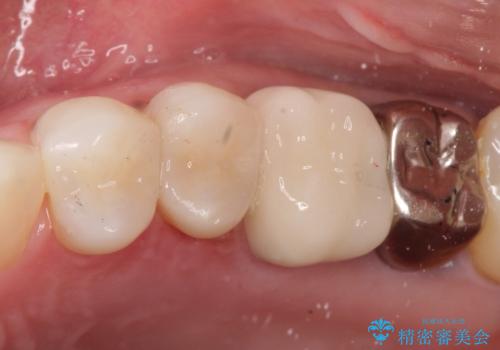

- 金属冠を白くしたいことを主訴に来院されました。

オールセラミッククラウン(st)にて修復しております。

根管治療も合わせて行なっているため、期間がかかっております。